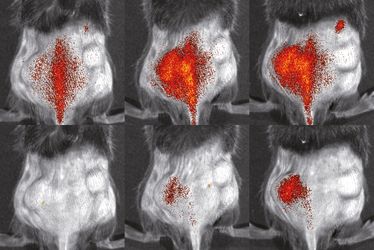

9. Small Animal Imaging Workshop - The Mouse Imaging Academy (MIA) Münster

9. Small Animal Imaging Workshop - The Mouse Imaging Academy (MIA) Münster

9. Small Animal Imaging Workshop - The Mouse Imaging Academy (MIA) Münster

9. Small Animal Imaging Workshop - The Mouse Imaging Academy (MIA) Münster